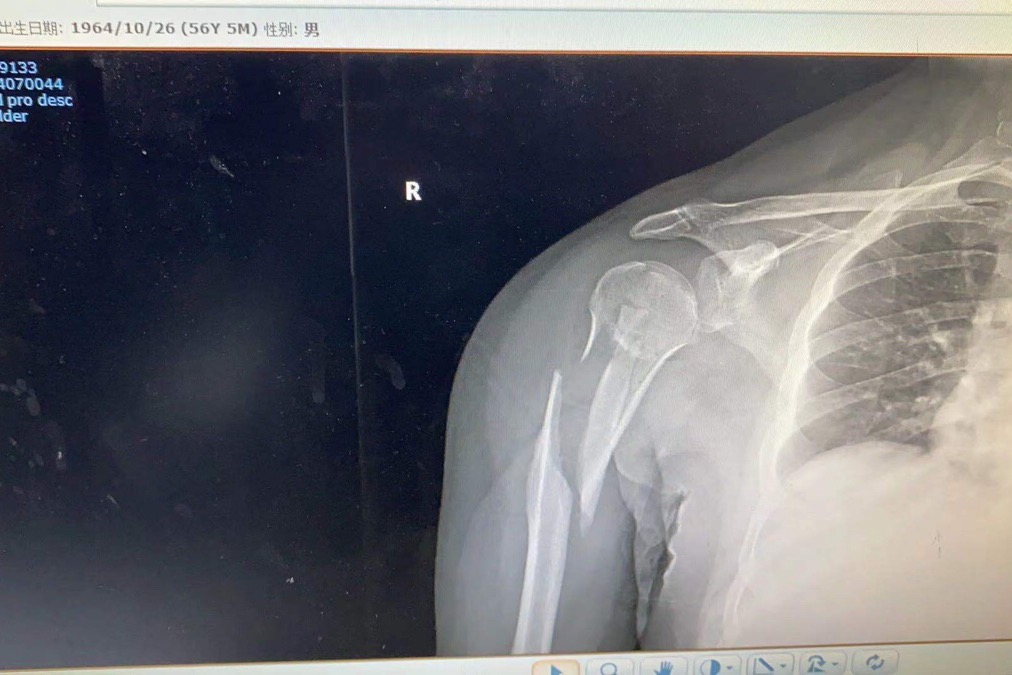

I am in Shanghai China and a hit and run driver accident from rear on my bicycle cause severe break to my right arm. I am a professional drummer but i may not be able to perform for several months. I don’t have insurance and the operation is $10,000.